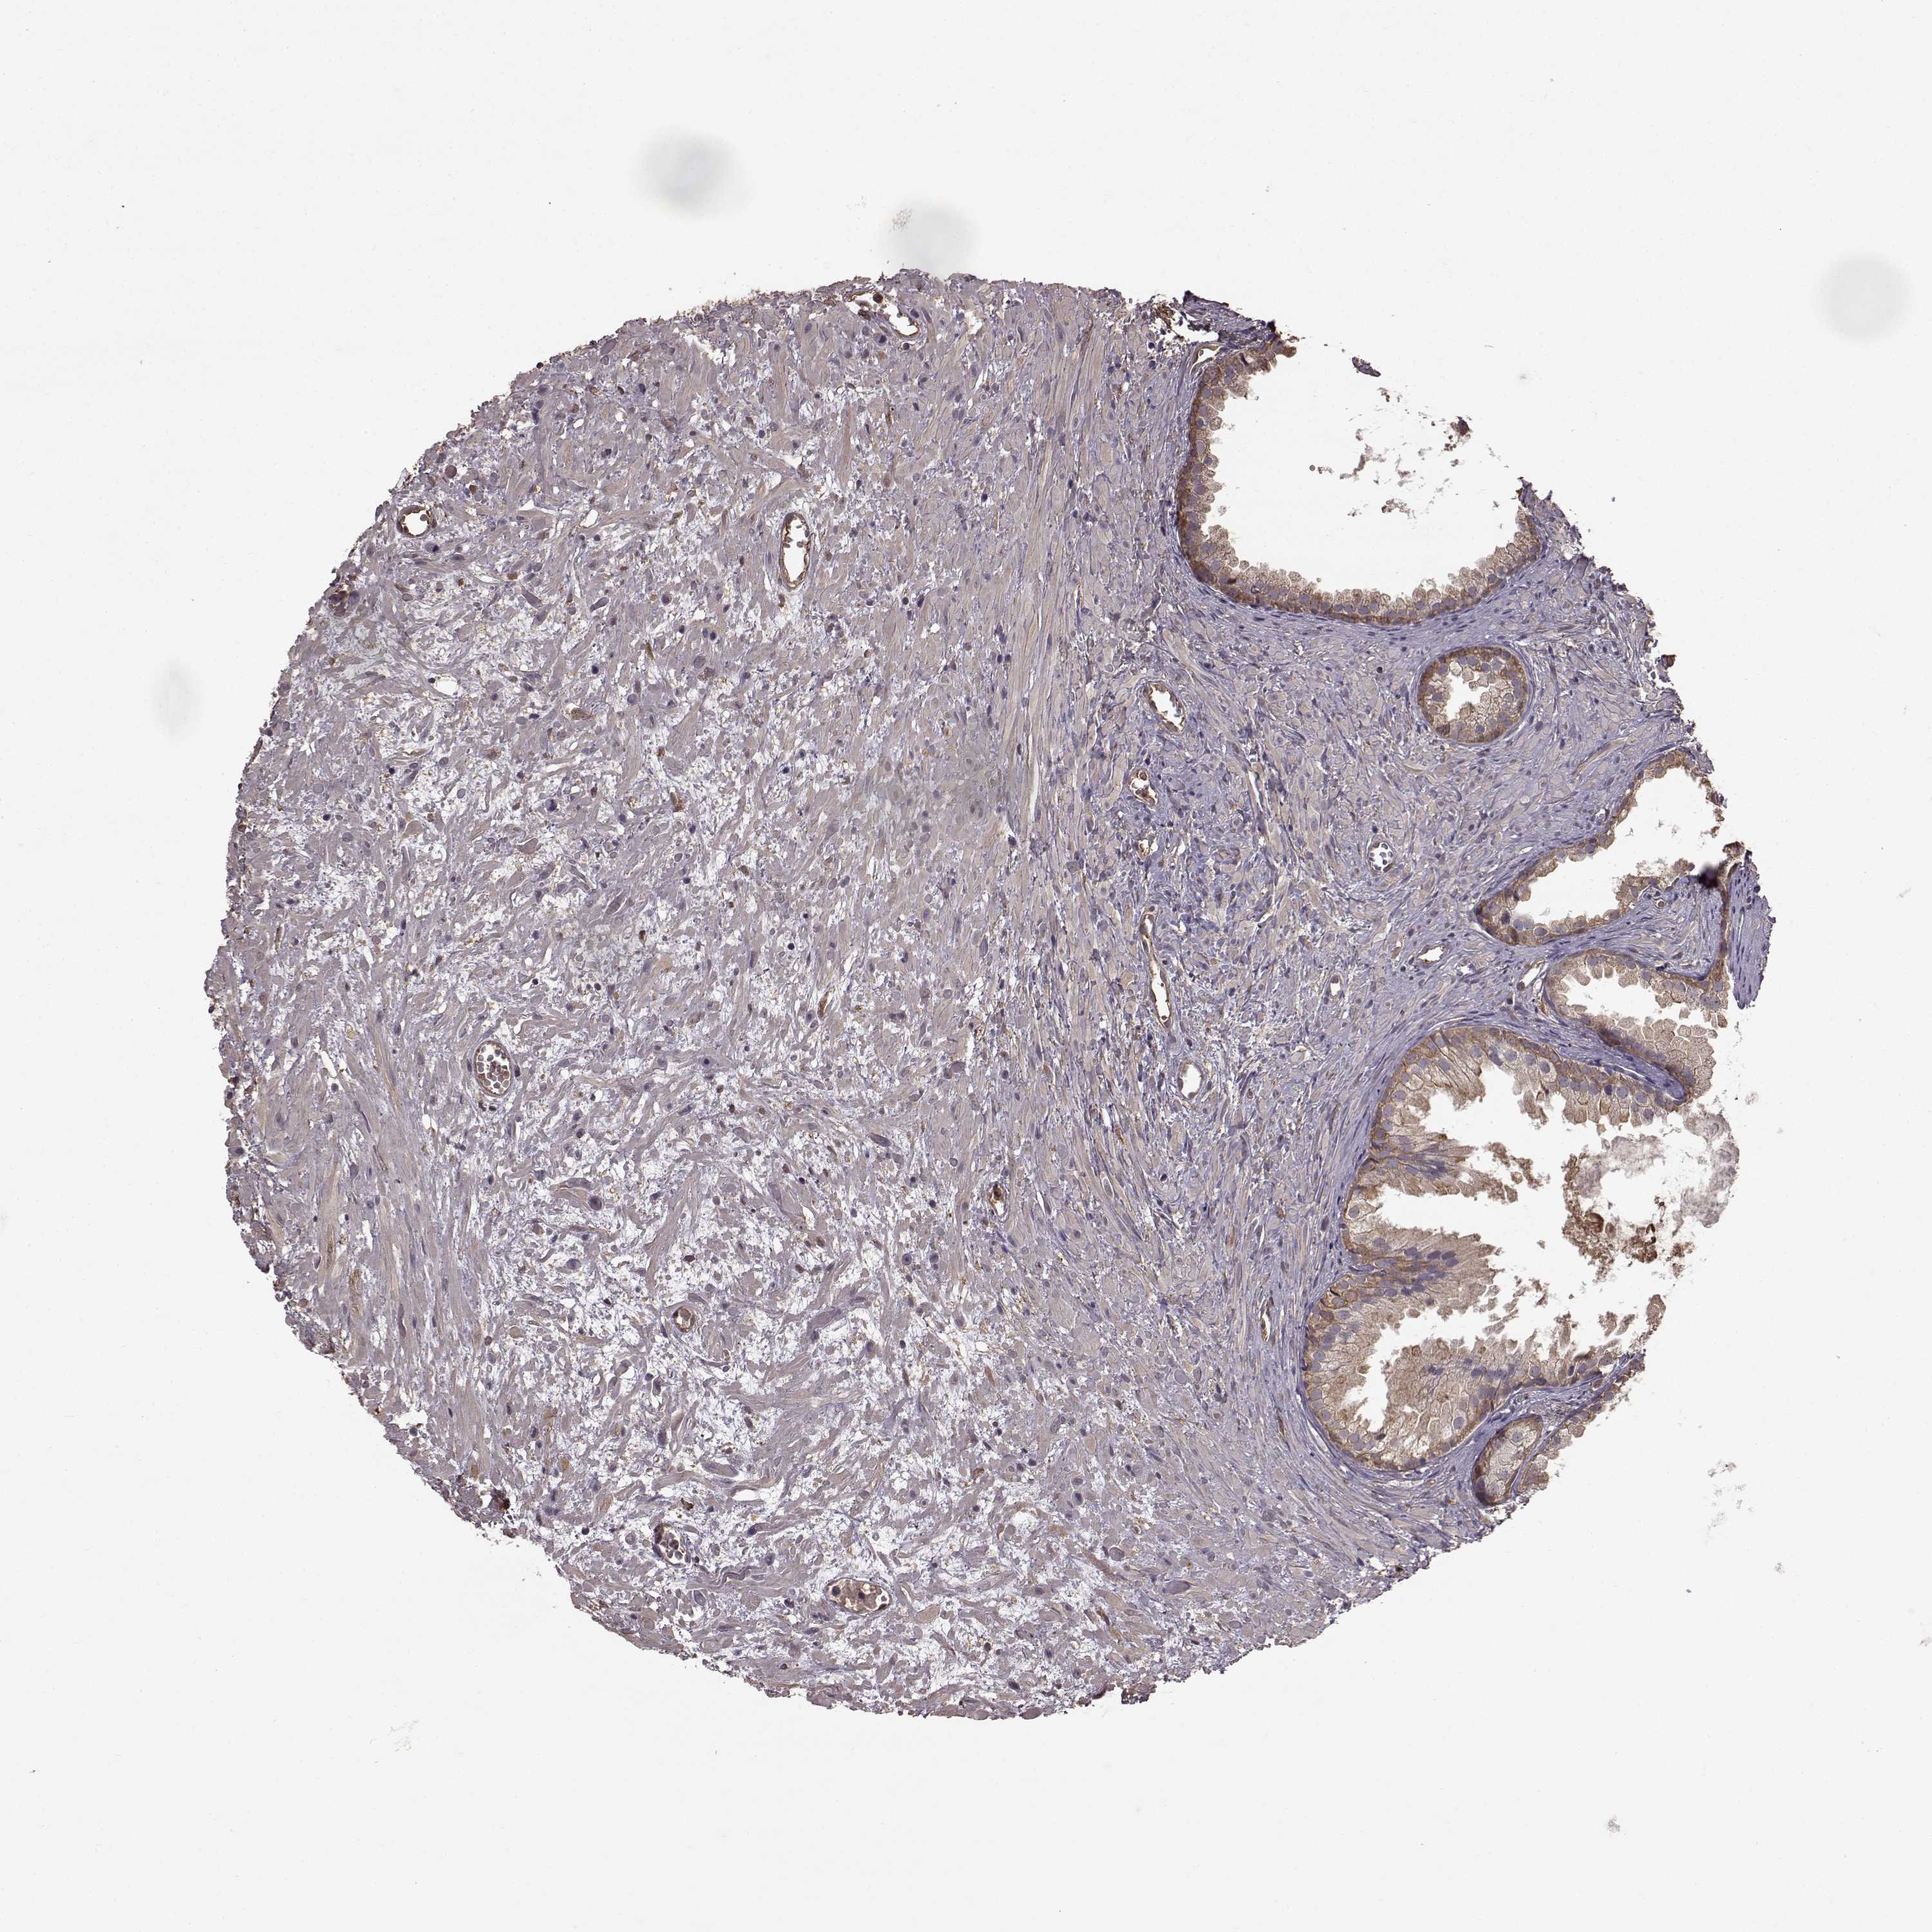

PROSTATE CANCER - Protein expressioni

A mouse-over function shows sample information and annotation data. Click on an image to view it in a full screen mode. Samples can be filtered based on level of antibody staining by selecting one or several of the following categories: high, medium, low and not detected. The assay and annotation is described here.

Antibody stainingi

Antibody staining in the annotated cell types in the current human tissue is reported as not detected, low, medium, or high, based on conventional immunohistochemistry profiling in selected tissues. This score is based on the combination of the staining intensity and fraction of stained cells.

Each image is clickable and will lead to virtual microscopy that enables deeper exploration of all samples and also displays staining intensity scores, fraction scores and subcellular localization as well as patient and tissue information for each sample.

Antibody HPA008467

Antibody HPA041113

Antibody CAB002169

Antibody CAB076057

Staining

High

Medium

Low

Not detected

Intensity

Strong

Moderate

Weak

Negative

Quantity

>75%

75%-25%

<25%

None

Location

Nuclear

Cytoplasmic/membranous

Cytoplasmic/membranous,nuclear

Adenocarcinoma, Low grade

Adenocarcinoma, High grade

Adenocarcinoma, NOS

Adenocarcinoma, Medium grade